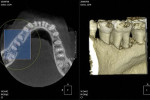

CBCT (cone beam computed tomography) is for everyone. It is not necessary to own one of these machines to use the data from it. CBCT data sets can be burned onto CD-ROMs or sent via the Internet to a dentist to open in third-party software such as implant-planning software or other viewing software. The impact of this technology has been rapid and universal.2-4 It is recommended that the general dentist use a “multifunctional” CBCT machine, one that can provide a conventional digital panoramic and other images and the software programs to create images such as those seen in this article, as well as cone beam information when desired or required.

It is the author’s opinion that “multifunctional” panoramic/CBCT machines are the most appropriate and the most cost-effective imaging devices for the general practitioner. Small-volume (small-FOV) CBCT machines require less “re-education” for the dentist because there is slightly less anatomy to rediscover and interpret. If you purchase a panoramic machine with CBCT capability, the panoramic and specialized panoramic images accelerate the ROI for the CBCT functions. With proper examination of the patient and the selection of the appropriate modality—panoramic, panoramic bitewing, and/or CBCT—your clinical decisions will be made more easily and more accurately, and your patient will benefit from more precise treatment.